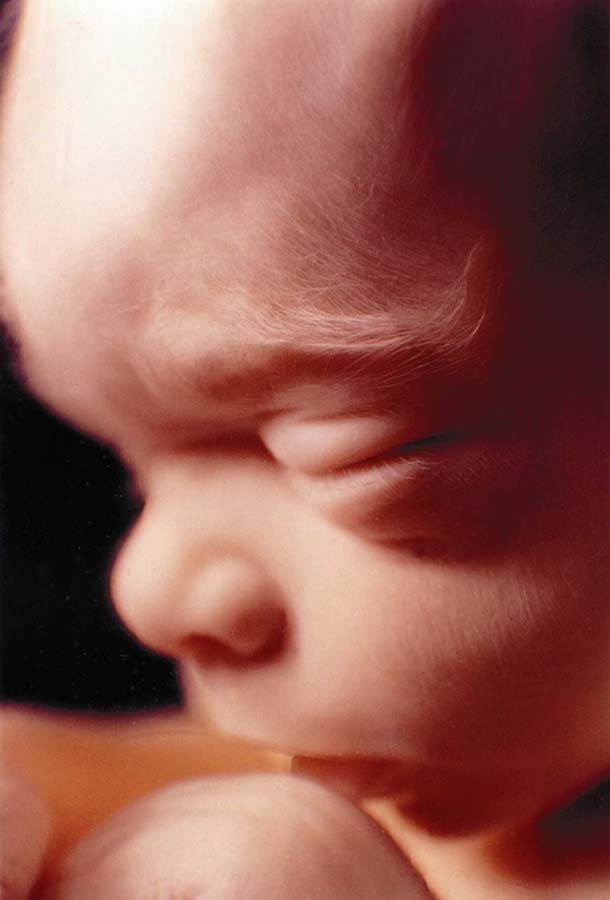

الجنين في الأسبوع الثامن:

الجنين في الأسبوع الحادي عشر:

الجنين في الأسبوع الثاني عشر:

الجنين في الشهر الثالث و النصف:

الجنين في الشهر الرابع،،

الجنين في الشهر الخامس،،

الجنين في الشهر السادس،،